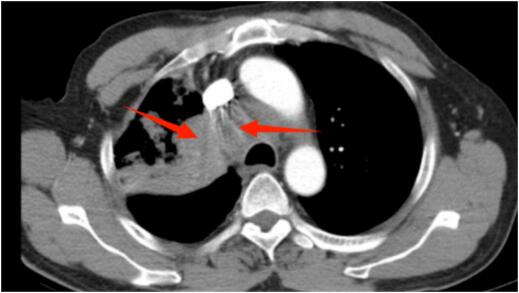

肿瘤科负责人、副主任医师王俊带领团队为魏先生行免疫治疗联合化疗后,影像资料显示肺部及纵隔病灶明显缩小,让魏先生的生活质量得到明显提高,临床症状完全消失。

治疗后